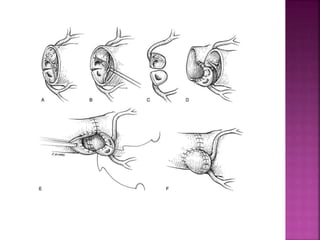

 Simple TGA – Neonates- Arterial switch within

1 month

 Simple TGA – after 30 days

 Pulmonary artery banding- Arterial switch

after 2 weeks

 Atrial switch

 TGA with VSD- Arterial switch within few

weeks

 TGA with VSD and LVOTO – repair - 6 months

 Simple TGA– Neonates- Arterial switch within 1 month  Simple TGA – after 30 days  Pulmonary artery banding- Arterial switch after 2 weeks  Atrial switch  TGA with VSD- Arterial switch within few weeks  TGA with VSD and LVOTO – repair - 6 months

 Establishing Ventriculo-arterialconcordance  Anatomical correction